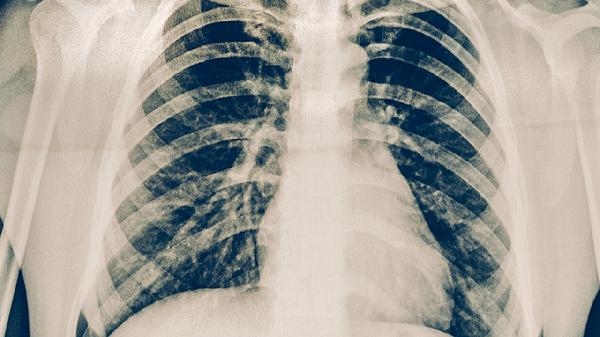

肺癌患者使用平消胶囊期间应保持清淡饮食,适当摄入优质蛋白如鱼肉、蛋类,避免辛辣刺激食物。建议进行八段锦等温和运动,定期复查CT评估疗效。出现发热、呼吸困难等症状需立即停药就医。心理疏导对改善治疗依从性具有重要作用,家属应给予充分情感支持。